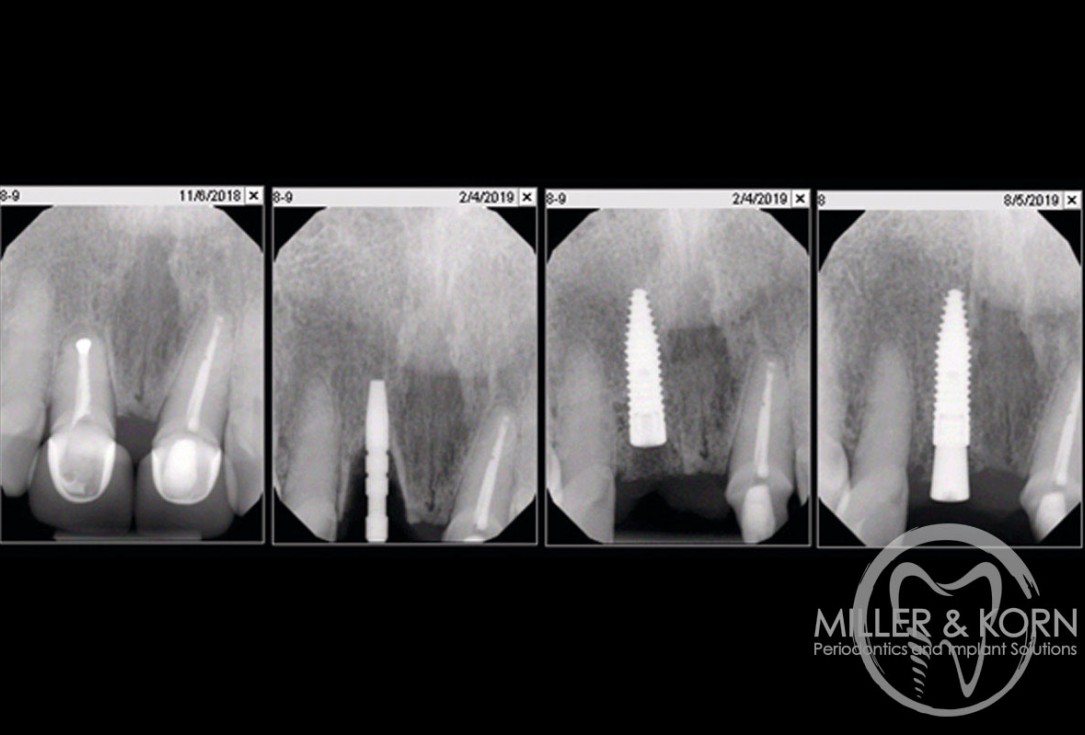

21/22 - Radiographs during therapy.Immediate implant placement and regeneration of ridge using an allograft bone ring and Jason® membrane - Drs. Miller and Korn

22/22 - Final radiograph one week post insertion.Immediate implant placement and regeneration of ridge using an allograft bone ring and Jason® membrane - Drs. Miller and Korn